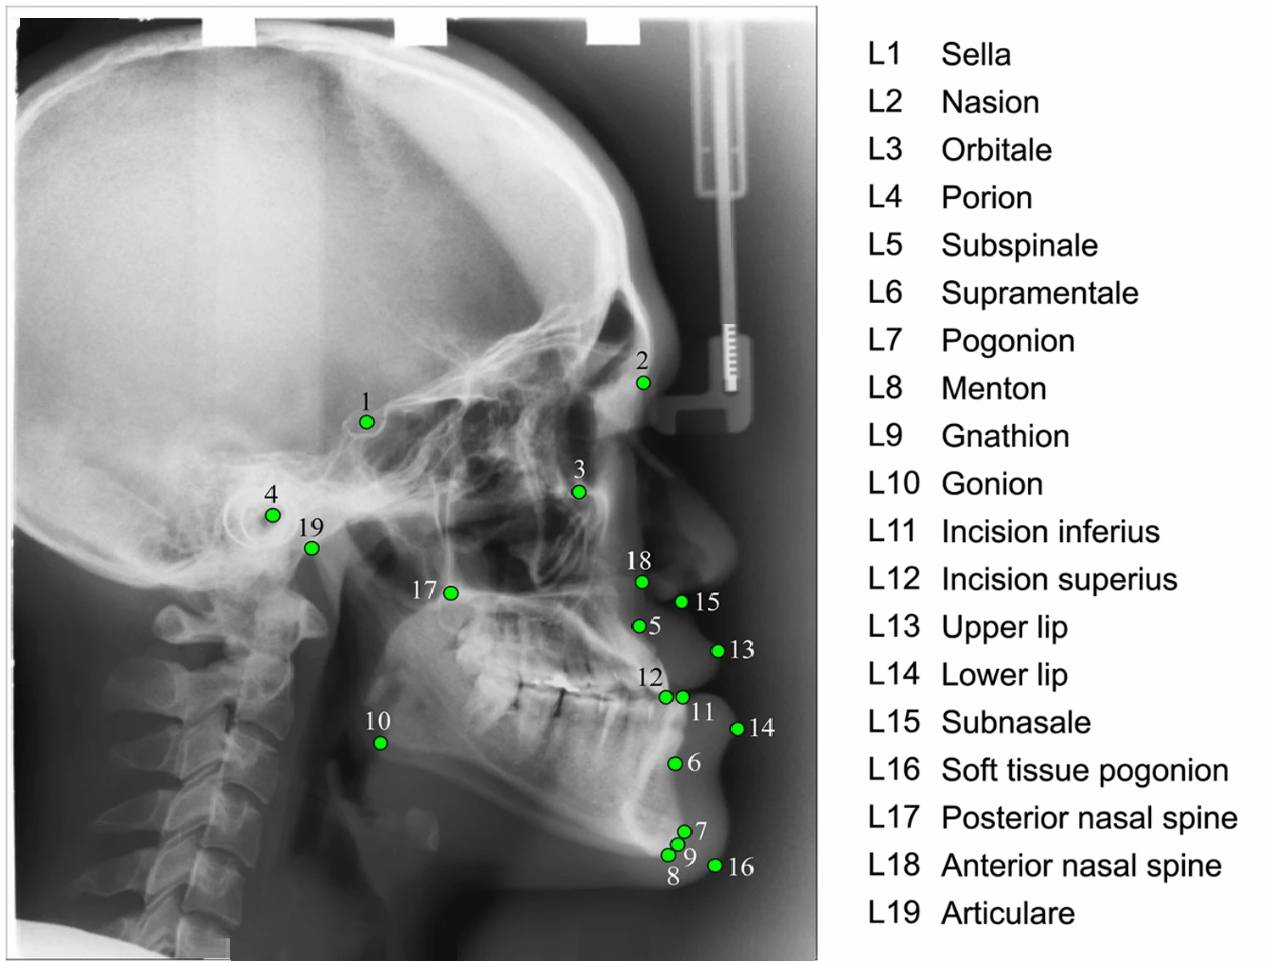

Orthodontic landmark detection involves

identifying specific points on radiographic images of the skull

(cephalograms) to assess craniofacial structures and guide orthodontic

treatment. These landmarks are used to measure angles and distances,

helping to diagnose dental and skeletal problems, plan treatment, and

evaluate results. Traditionally, this process was done manually, but

automated landmark detection using artificial intelligence (AI) is

increasingly being used to improve efficiency, accuracy, and consistency. In summary,

orthodontic landmark detection is a crucial aspect of orthodontic diagnosis

and treatment planning. While manual methods are still used, the rise of

AI-based systems promises to enhance the efficiency, accuracy, and

reliability of this process. PUPILLA™ is an

them. Below we explain how the PUPILLA™ algorithm

works in an example of determining the position of the L2 point (Nasion),